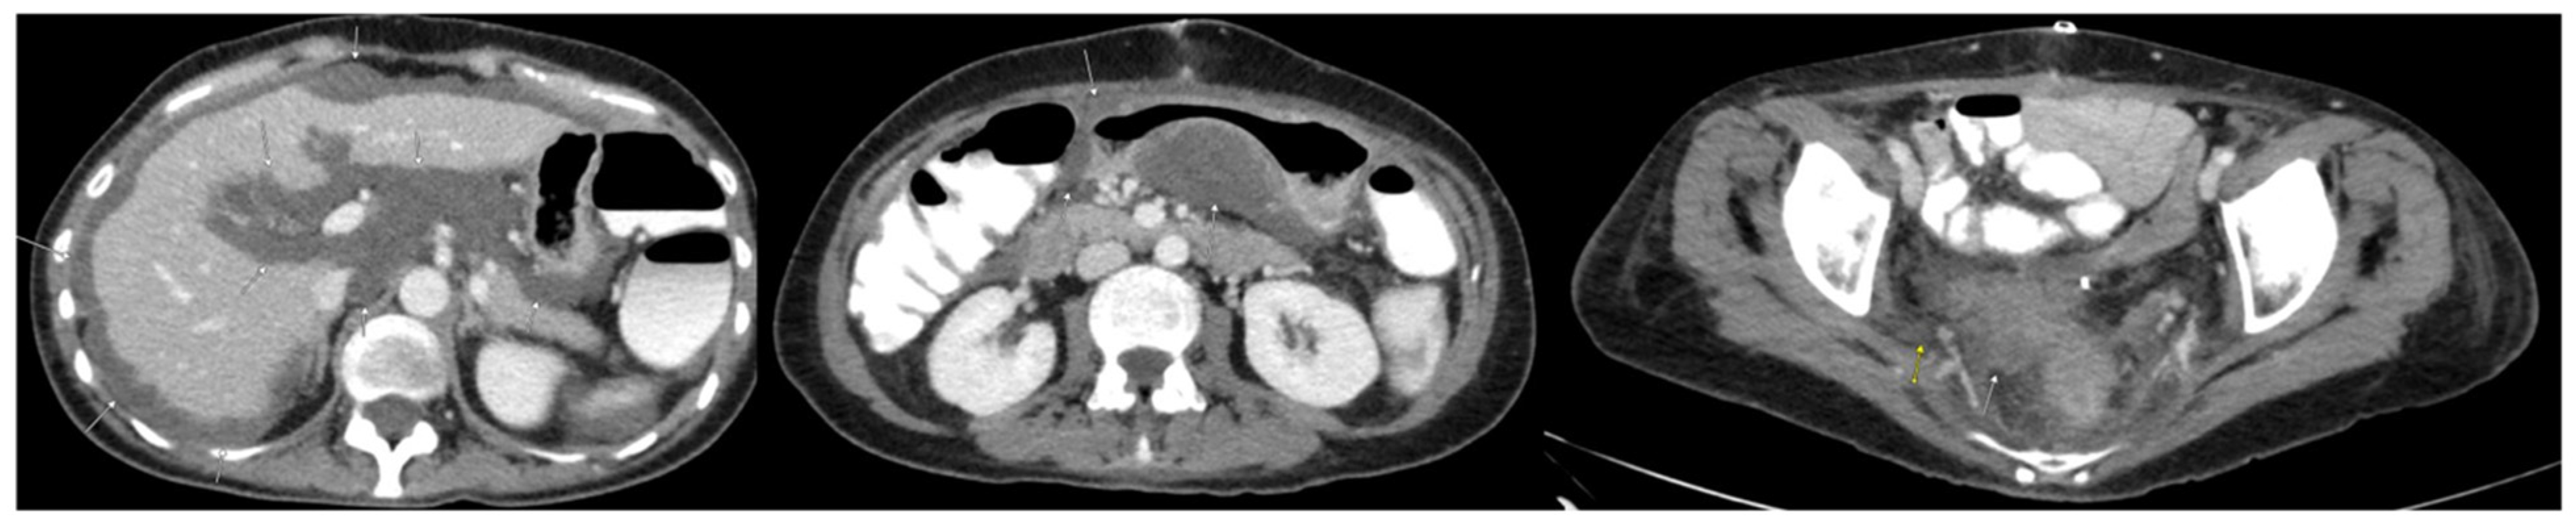

2. Case